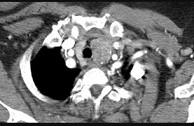

问题 40岁,女,发现颈部肿块,随吞咽上下移动,触之无搏动,咳嗽、气喘一周,请结合CT检查选择最可能的诊断()

选项 A.胸腺瘤 B.胸内甲状腺瘤 C.无名动脉瘤 D.无名动脉伸展扭曲 E.淋巴瘤

答案 B